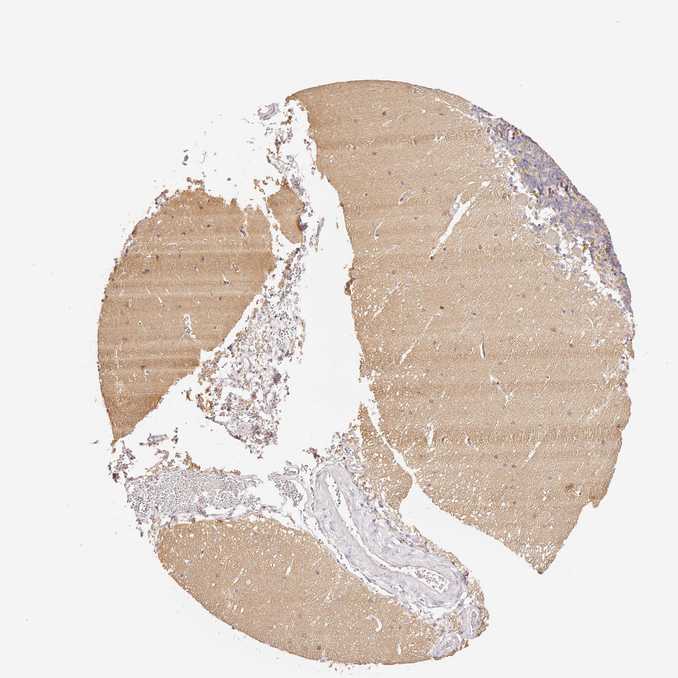

CEREBELLUM - Antibody stainingi

Antibody staining in the annotated cell types in the current human tissue is reported as not detected, low, medium, or high, based on conventional immunohistochemistry profiling in selected tissues. This score is based on the combination of the staining intensity and fraction of stained cells.

Each image is clickable and will lead to virtual microscopy that enables deeper exploration of all samples and also displays staining intensity scores, fraction scores and subcellular localization as well as patient and tissue information for each sample.

Antibody HPA030266

Purkinje cells Not detected

Cells in granular layer Not detected

Cells in molecular layer Not detected